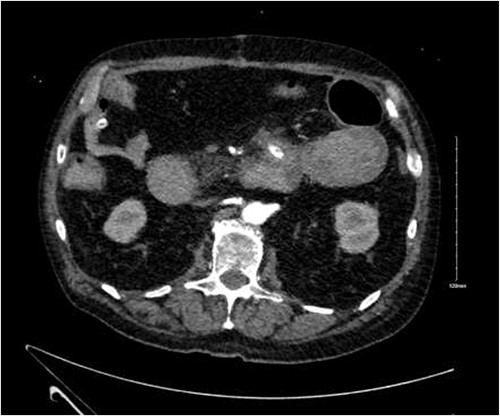

CTA demonstrated angiodysplasia in the duodenal diverticulum at the duodenojejunal junction with associated contrast blush (Figs 1 and 2). The urgent opinion of an interventional radiologist was sought in a tertiary centre. The patient was accepted for urgent embolization in an attempt to stabilize the patient. The patient required an intra-hospital transfer overnight.